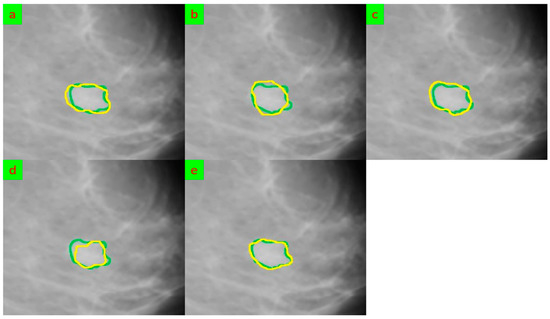

3.4. Experimental Results

- State-of-the-Art Performance: The abstract states that the proposed methodology demonstrates state-of-the-art performance on the Mini-MIAS dataset, surpassing existing methods in terms of accuracy, sensitivity, and specificity. Achieving high accuracy and sensitivity is crucial in clinical applications to ensure that breast tumors are correctly identified and localized. The improved performance of the proposed model suggests its potential to provide reliable and accurate results for clinical decision-making;